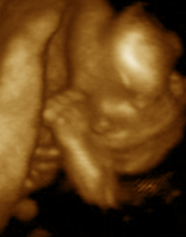

Dos escenas de videos. La de la izq. uno de los gemelos alcanza y "acaricia" la espalda de su hermano. la de la derecha, uno de los gemelos acaricia la cabeza de su hermano.